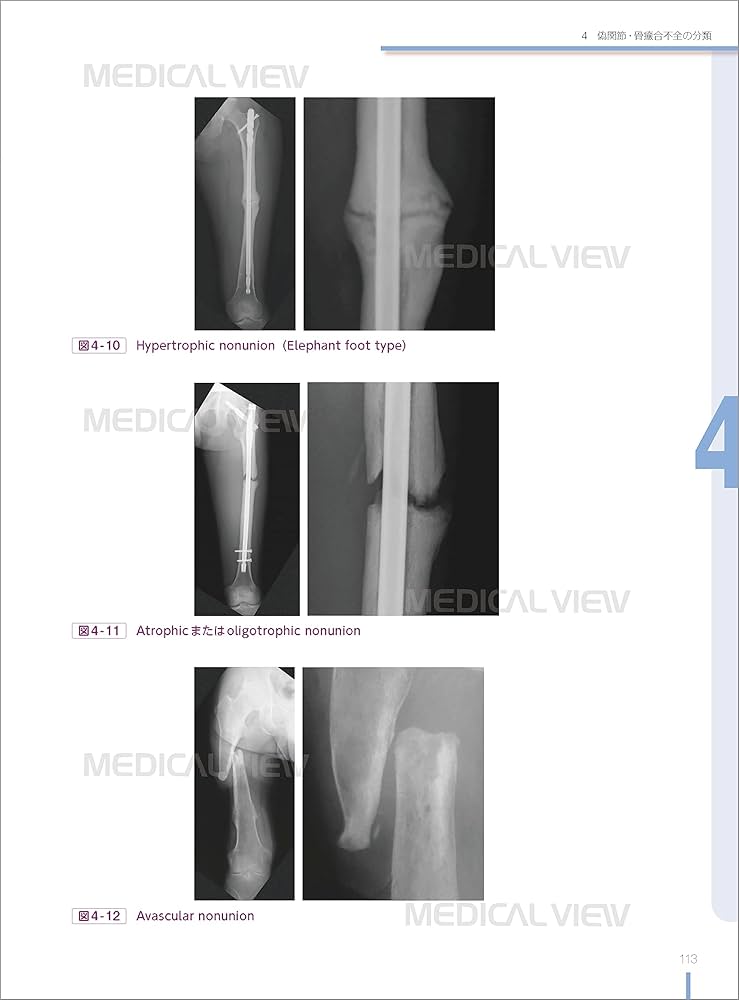

「骨折合併症 : 白熱講義 : 骨折治療の物理学と生物学 : Nonunion,Malunion,FRI,PTOA」渡部 欣忍定価: ¥ 13000裁断済み商品のため、状態悪いにさせていただいております。 裁断済みにご理解のある方のみご購入願います。 多少のお気持ち程度のお値下げ交渉は応じます 状態については写真の通りです。 見たところ概ね書き込みはありません。 #医学 #研修医 #医療 #レジデント #病院 #整形外科 #骨折#渡部欣忍 #渡部_欣忍 #本 #自然/医療・薬学・健康